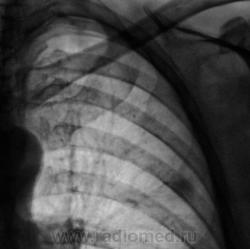

При расшифровке флюорограмм пациент взят на контроль. Ваше мнение уважаемые коллеги?

Тоже думали, гадали. Тень на уровне 3 ребра слева показалась "копеечной", не заслуживающей внимания?

Но "стандарт", есть "стандарт". Была произведена линейная томография в прямой проекции.

И. конечно, "тень" слева, вызвала самые серьёзные подозрения.

И правильно сделала. У Розенштрауха, Рыбаковой и Виннер есть картинка малого рака один в один.

Возможно, я не совсем ясно выразился, но тень слева, та, что на рентгенограмме на уровне 3 ребра весьма похожа, и очень, на неопластический процесс.

"Подтекст", именно в том, что, кроме указанной тени, были обнаружены и очаги, генез которых не вызывает сомнения.

Да, слева "лучезарная тенюшка" расценена, как онкология.